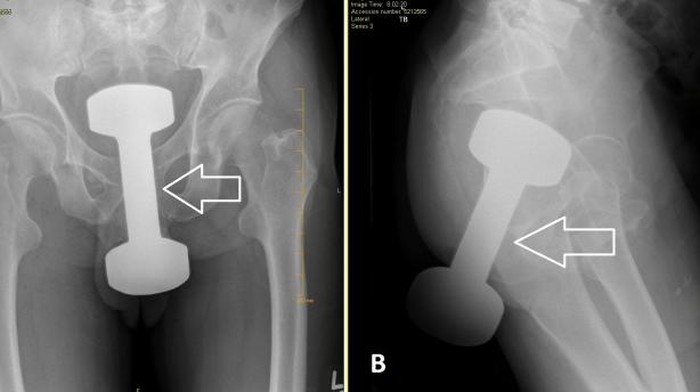

"Radiografi abdomen biplanar memperlihatkan adanya bayangan benda asing radiodense di garis tengah panggul yang konsisten dengan riwayat adanya dumbell lima pon. Tim bedah kemudian dikonsultasikan," lanjut laporan tersebut.